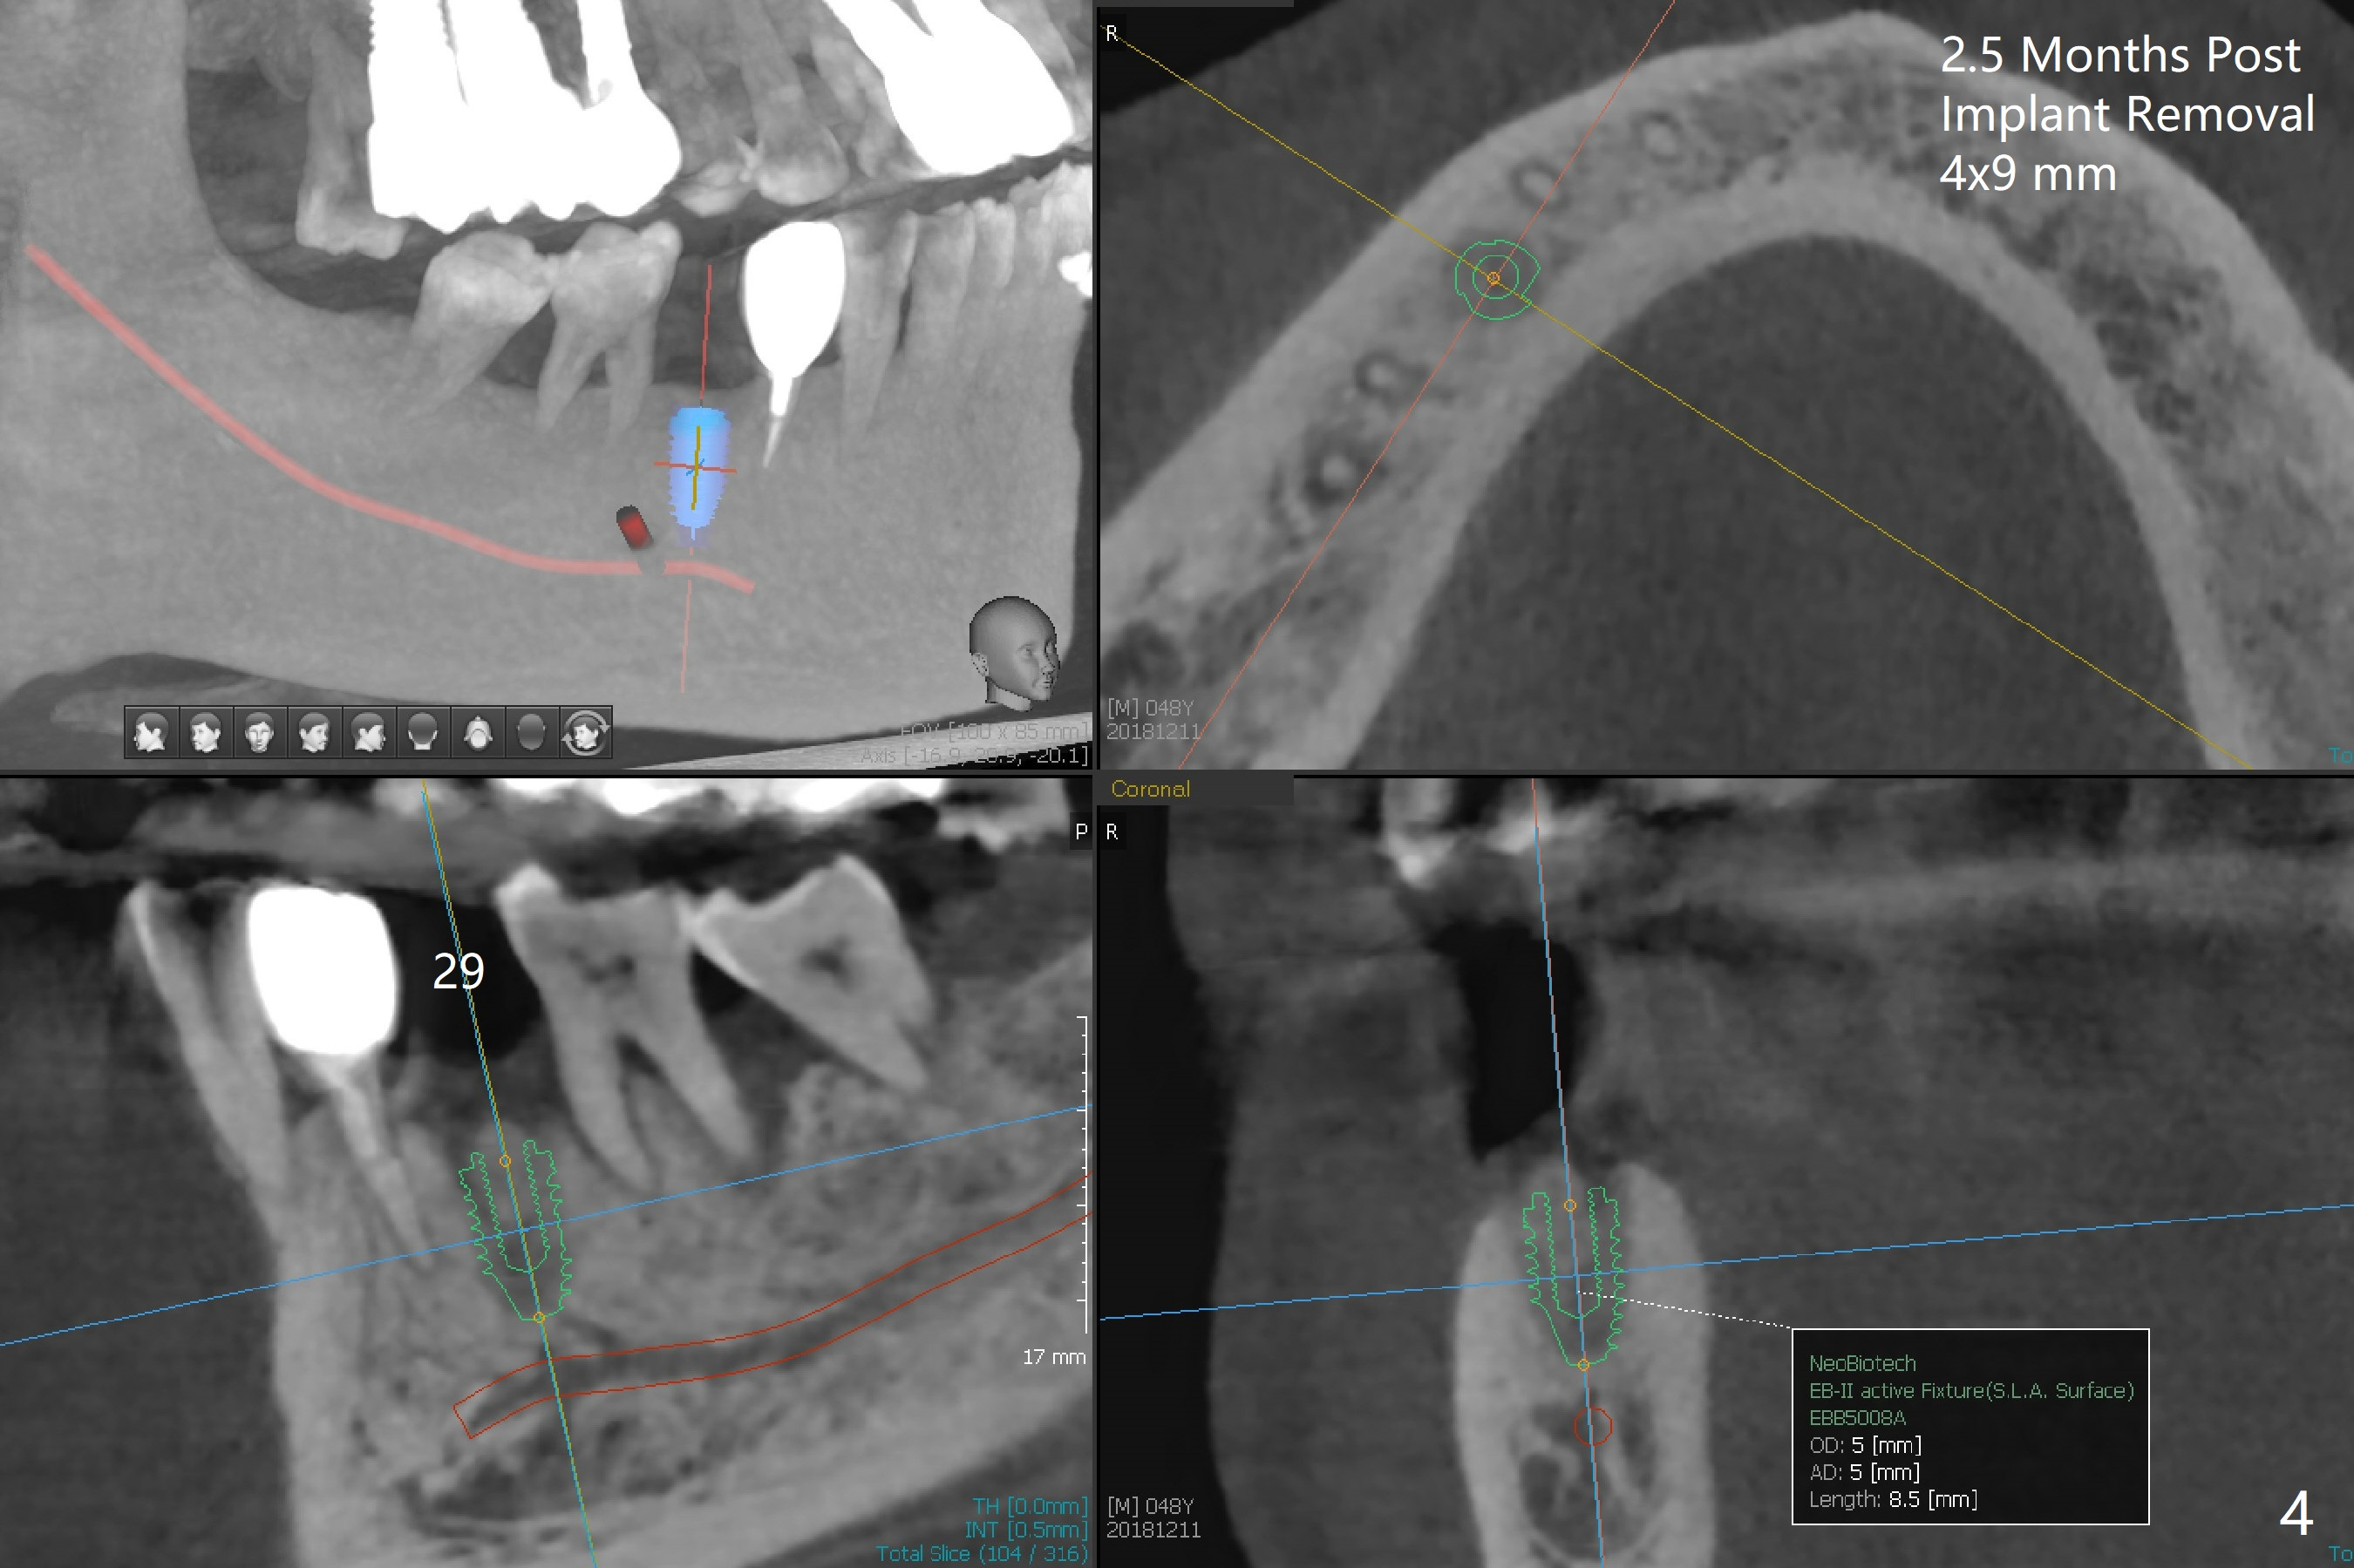

A 48-year-old man returns for implant placement at #14,15 and 29 (5 months post implant removal, 1 year post extraction and 2.5 months post implant removal, respectively, all with bone graft, Fig.1). Since the bone height at #14 and 15 is sufficient and sockets heal, implant placement will be done first (Fig.2,3), as compared to those at #29 (Fig.4). The tooth #18 is periodontally compromised with buccally cross bite (Fig.1); the position of the implant at #15 will be set up normally. When the site of #29 is ready for implant, use a large one (4.5 or 5x8.5 mm; use a dummy one as a tap).